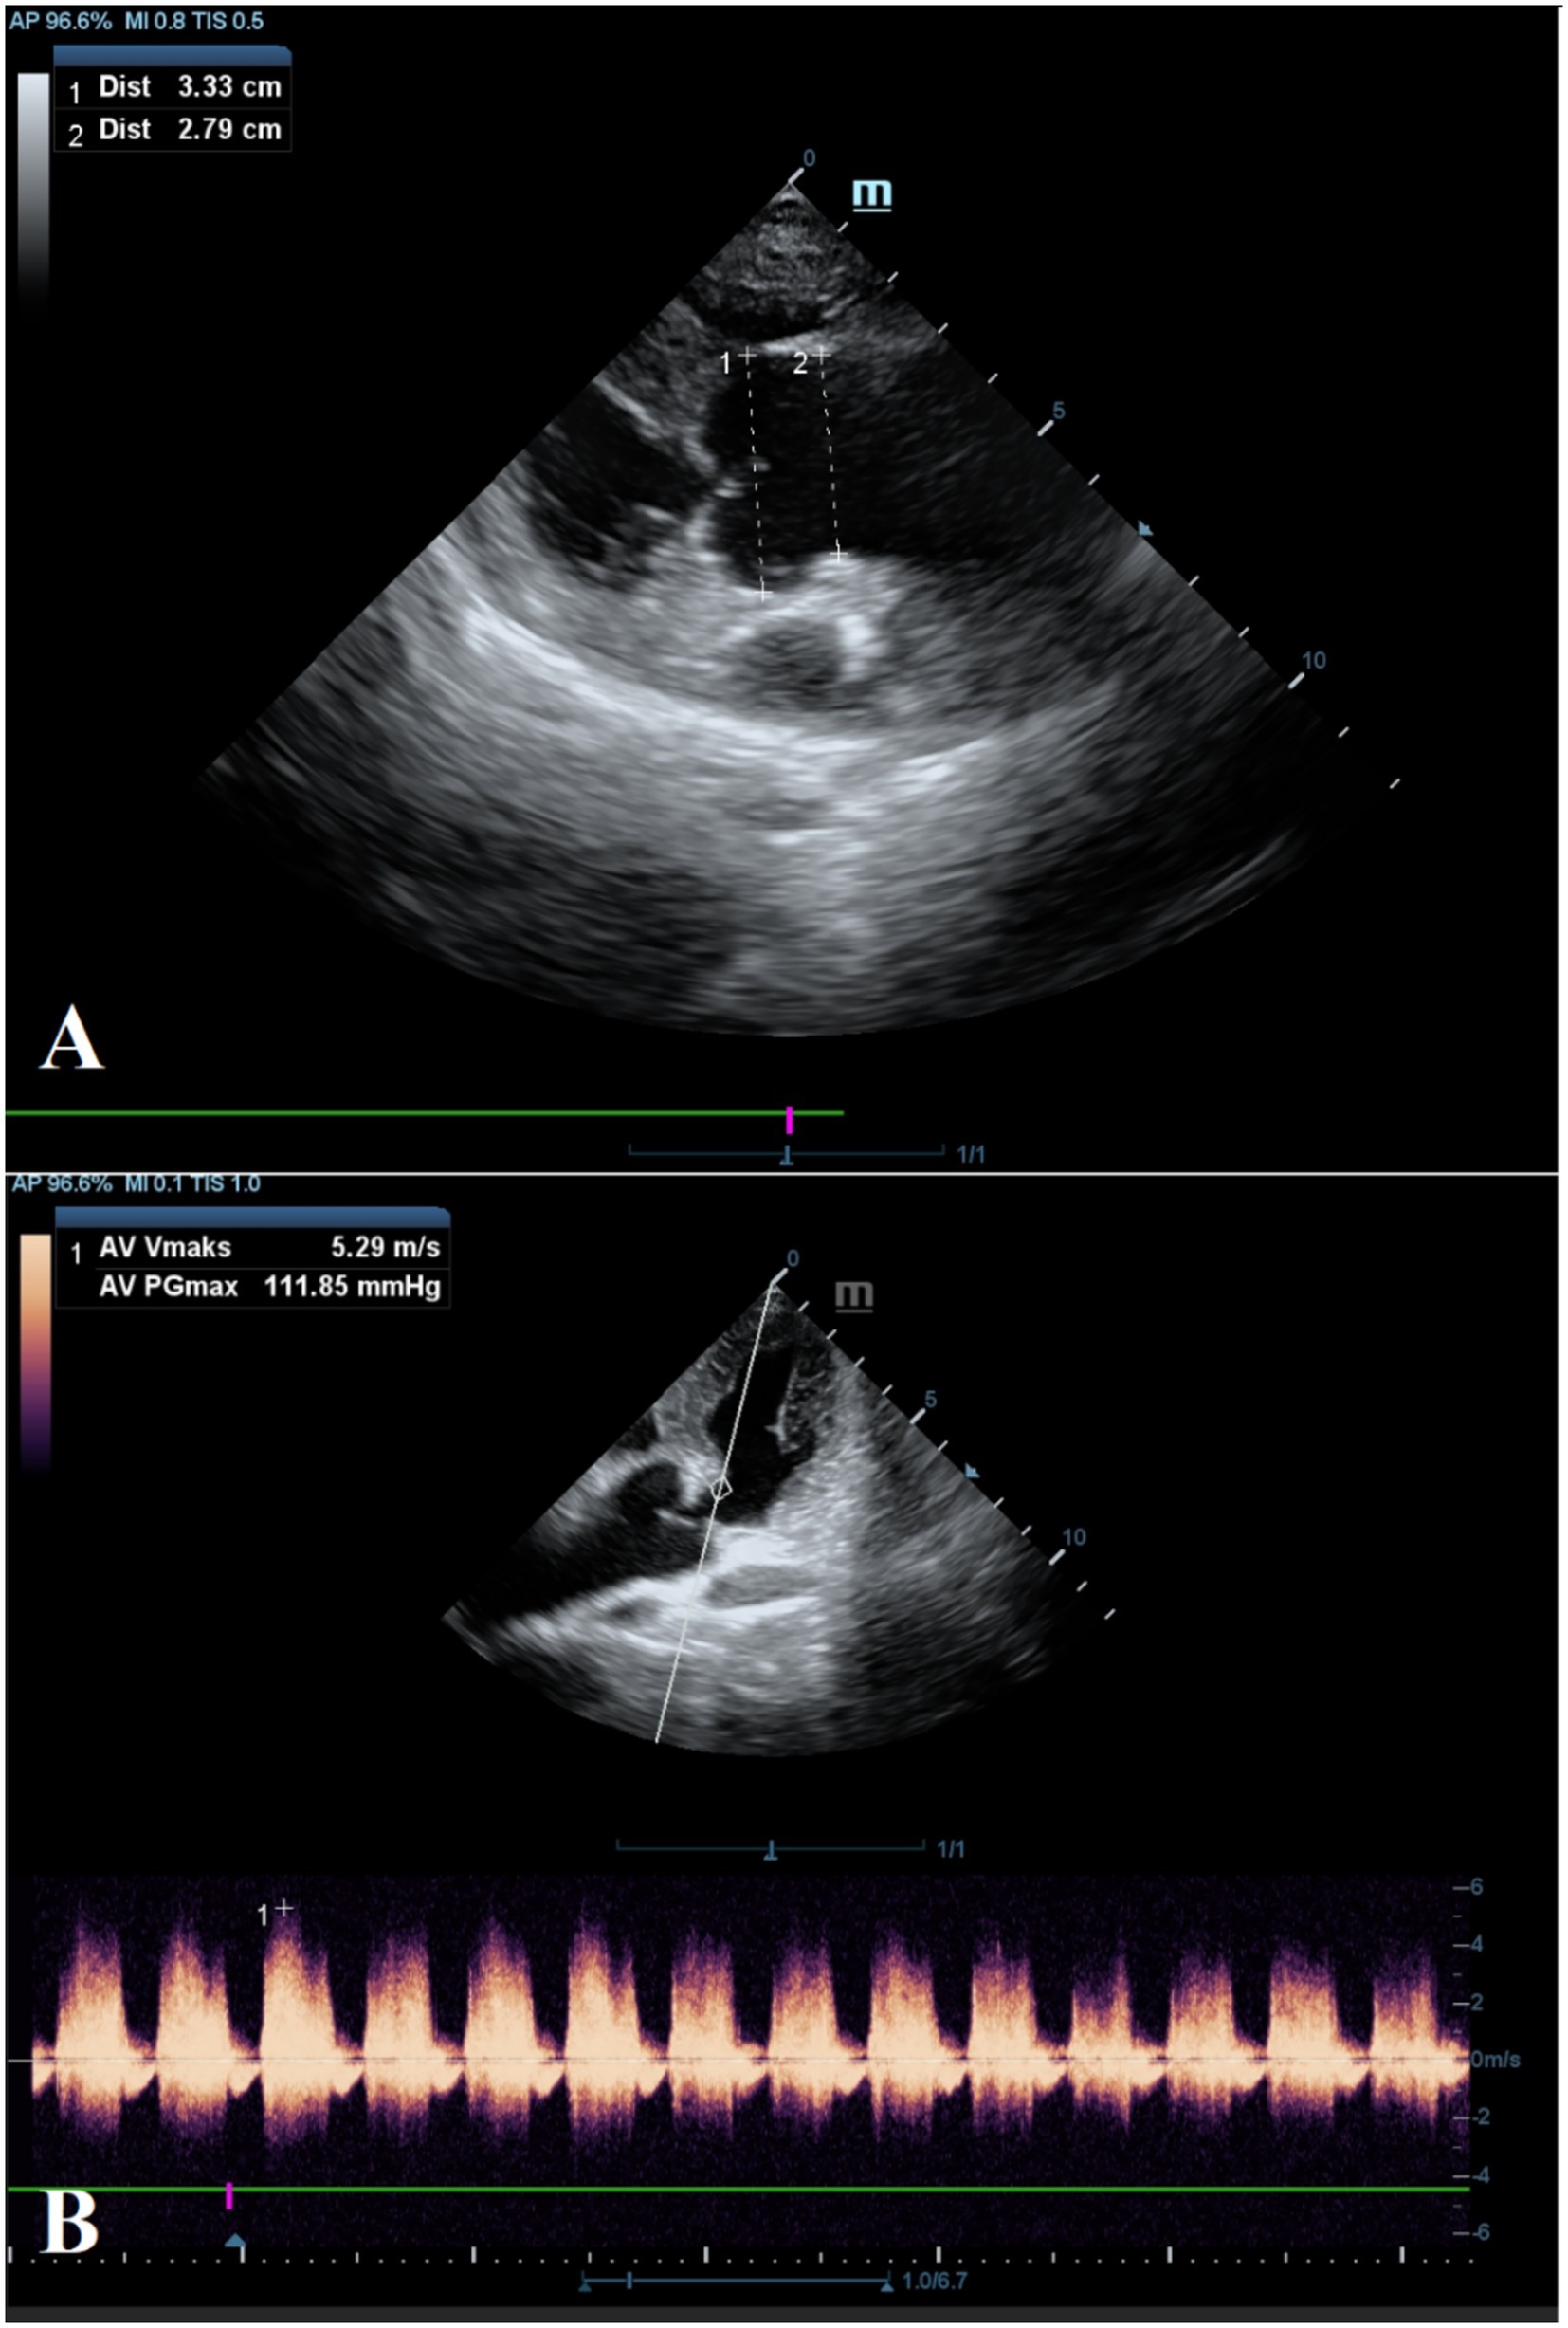

Electrocardiographic evaluation revealed a prolonged PR interval of 0.28 s. Echocardiographic examination revealed aortic regurgitation (5.29 m/sn), a maximal pressure gradient of 111.85 mmHg, and dilation of the aortic root and proximal ascending aorta in the parasternal long-axis view (Figure 2). The left ventricle was mildly enlarged, and the left atrial diameter was within reference ranges (Table 1). The aortic valves, commissures, and rings reflected natural anatomical structures. Mitral valve degeneration with mild regurgitation (<2 m/sn) and tricuspid valve regurgitation (2.73 m/s) was observed, without right atrial enlargement. No cardiac defect was detected.

Figure 2. Echocardiographic evaluation of the aorta. Dimensions of the sinuses of Valsalva (1) and the sinotubular junction (2) (A). Aortic valvular regurgitation with a maximal velocity of 5.29 m/s and a pressure gradient of 111.85 mmHg (B).

Among the most common acquired etiologies of aortic regurgitation are degenerative or atherosclerotic changes of the aortic valve associated with aging, systemic hypertension, and hyperlipidemia. These processes impair cusp coaptation during diastole, resulting in retrograde flow from the aorta into the left ventricle (14). Age-related factors, in particular, contribute to reduced leaflet elasticity, increased leaflet thickness due to the accumulation of adipose tissue between the fibrosa and ventricularis layers, deposition of extracellular matrix components and cellular degradation products, and increased collagen fiber density. Collectively, these changes lead to leaflet stiffening and reduced compliance. Over time, this degenerative progression results in valve thickening, rigidity, and calcification, ultimately causing progressive narrowing of the valvular orifice (15). Chronic exposure to high-velocity, turbulent blood flow distal to the valve promotes further vascular remodeling, especially at the level of the sinuses of Valsalva and the sinotubular junction (16). The severe aortic regurgitation and distal aortic dilation observed in the present case are consistent with these pathological mechanisms. However, due to the owner’s refusal of necropsy, histopathological examination of the aortic wall could not be performed.

Aortic remodeling associated with loss of aortic elasticity and aortic root dilation secondary to systemic hypertension has been previously reported in dogs (7, 17). In the current case, despite chronic aortic regurgitation with a regurgitant jet velocity of approximately 5.29 m/s, the patient remained normotensive. In human medicine, aortic regurgitation in normotensive individuals has been associated with advanced age, female sex, fibro-calcific changes of the aortic valve, and low body mass index (18). In this case, despite the presence of both aortic and mitral regurgitation, systemic arterial blood pressure and echocardiographic indicators of left heart filling pressures remained within normal limits. This suggests that the patient was still in a compensated phase, during which forward stroke volume is preserved and both the left ventricle and left atrium exhibit increased compliance.